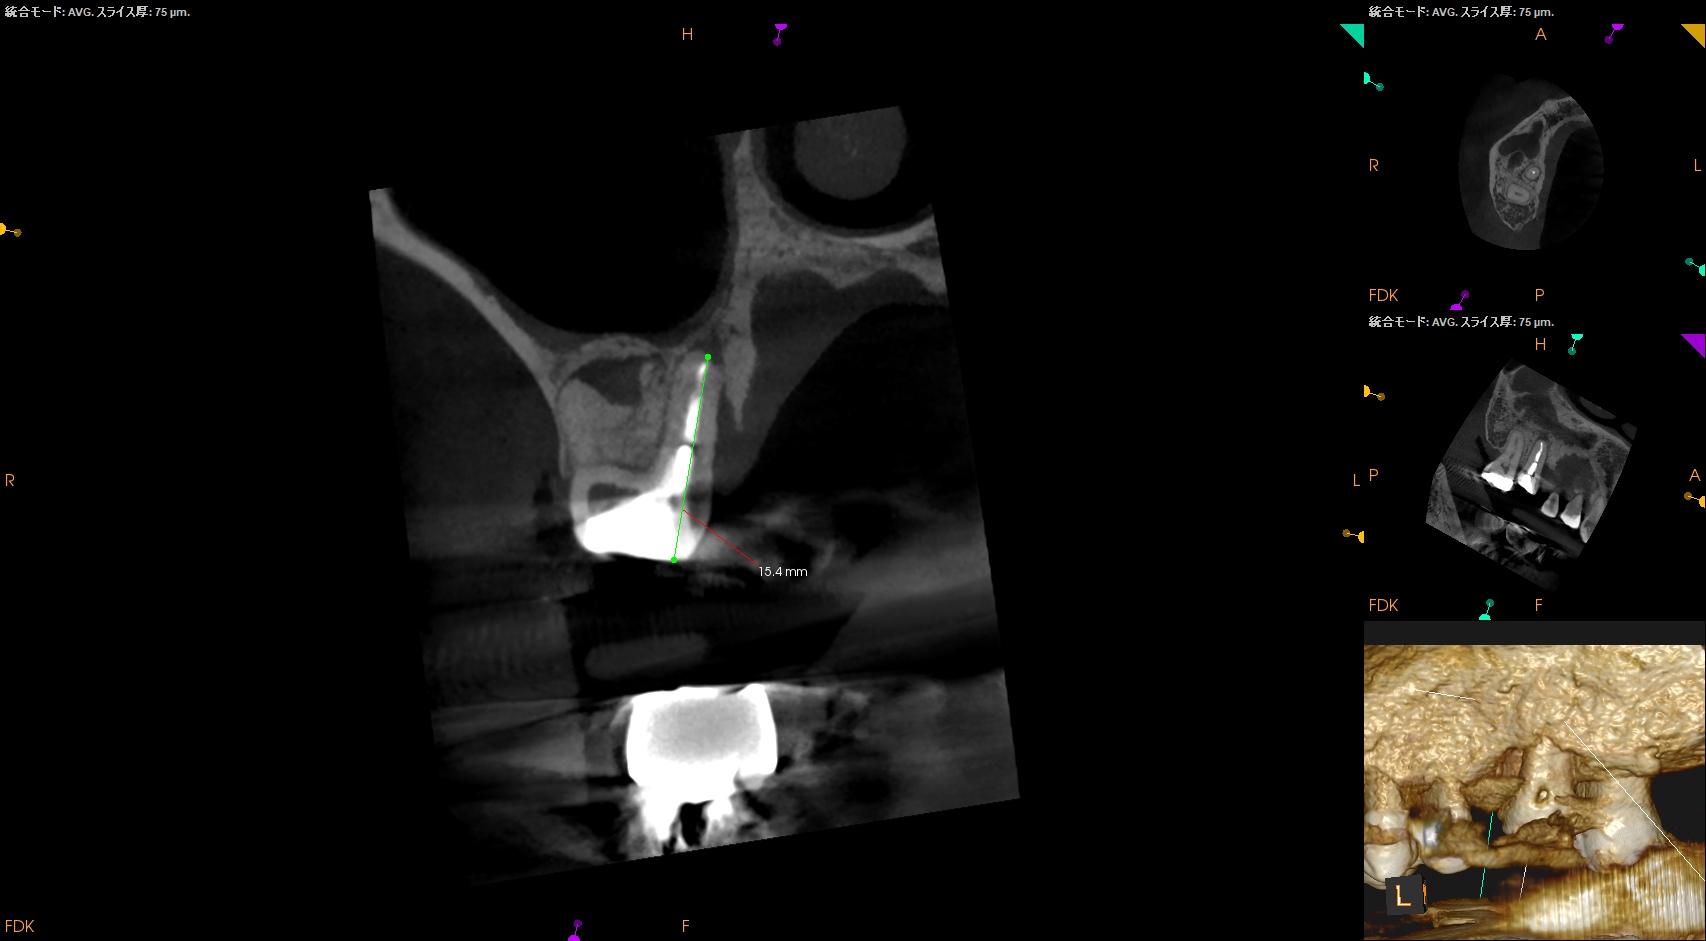

ちなみにPの再根管治療は、

作業長は16.0mm前後が予想される。

その際の作業長はCBCTから16.0mmである。